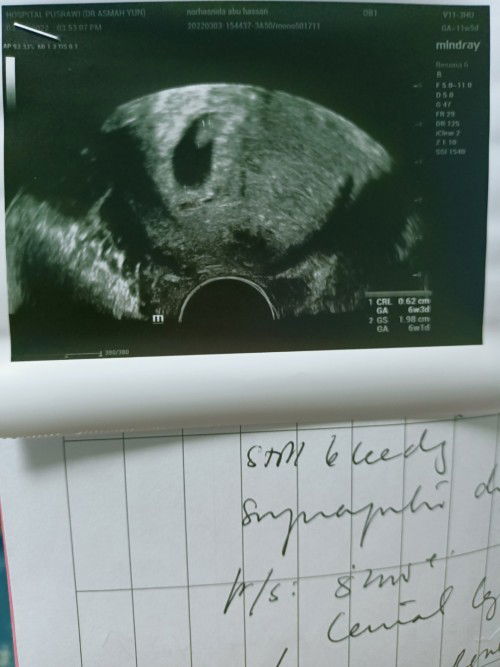

Hi mummies semua..hari ni 2nd appointment dng speacialist..Ikut kiraan saya dah 11w 5d tp dekat scan baru 6w 3d ..doc ckp kantung ok..tp check heartbeat baby x de lagi ..and doc ckp threatened misscarriage sbb bleeding tak berhenti walaupon da naik kan dos duphaston 3x sehari .. so doc Tanya nak injection kuat kan rahim?? and I say yes and still smbung duphaston for 1 more weeks .. next Thursday check up lagi sekali... Mommies ade pengalaman mcm saya??and saya perlu kan kata2 semangat dari mommies semua 😔😔 #ingintahu #sharepengalamanbunda #bleeding #katakatasemangatandadiperlukan